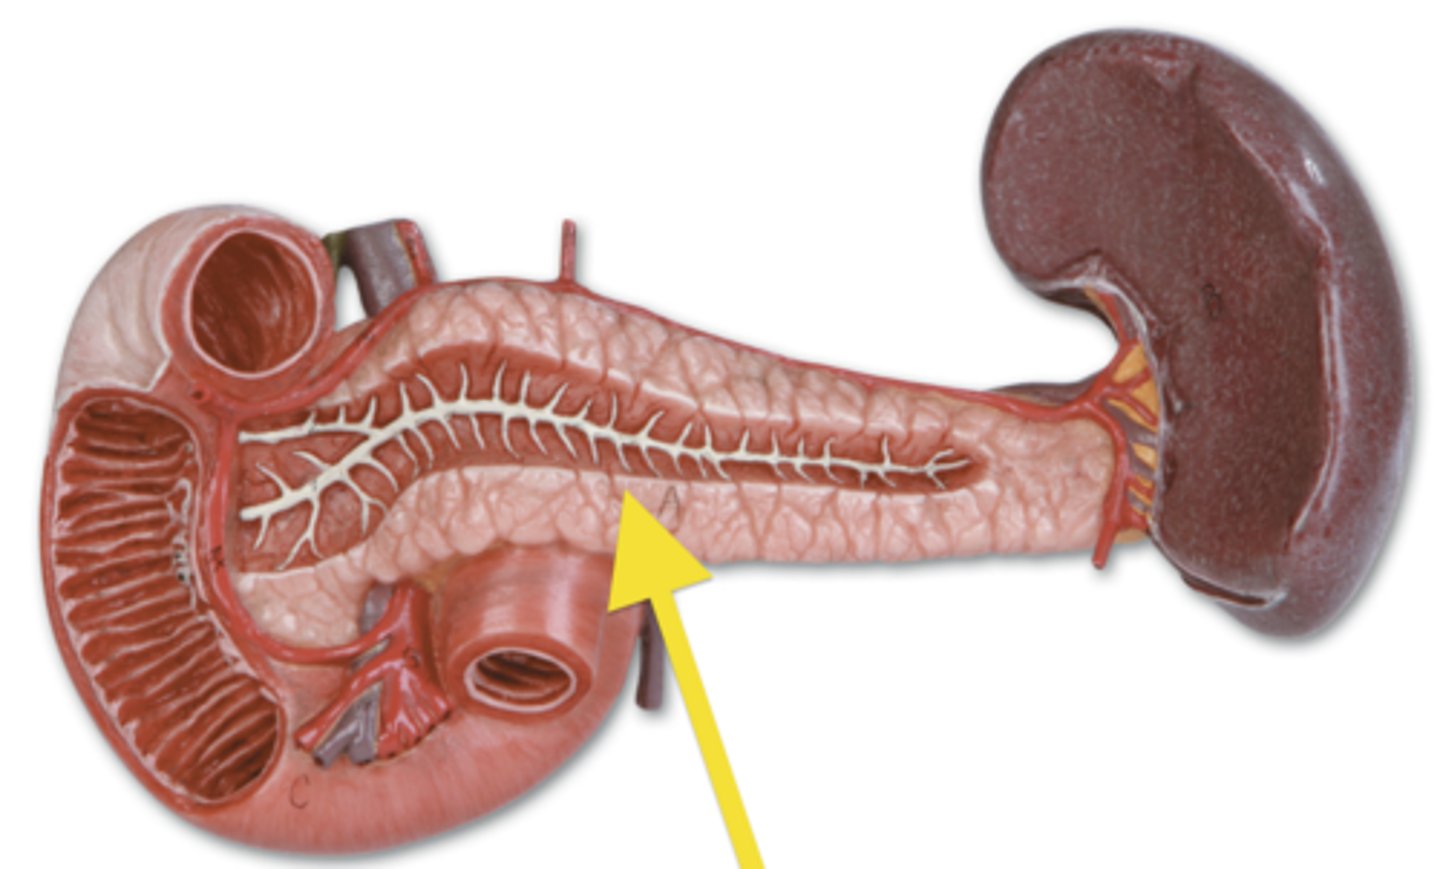

pancreas

organ

spleen